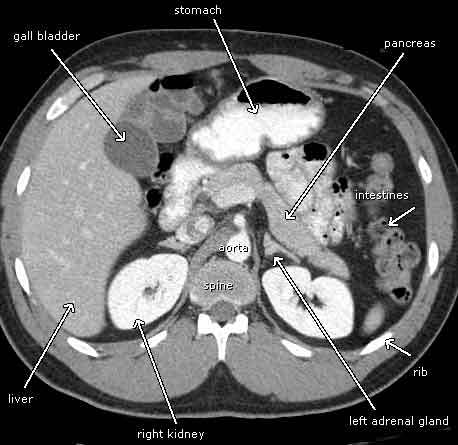

How does a CT scan work?

Rotating X ray tube + opposing detector

Computer reconstruction of axial cross-sectional images, based on X rays

What is a CT with contrast and what is it used for, when is it to be used with caution?

Outlines GI tract, used to delineate vascular structures + demonstrate tumour enhancement

Can be nephrotoxic